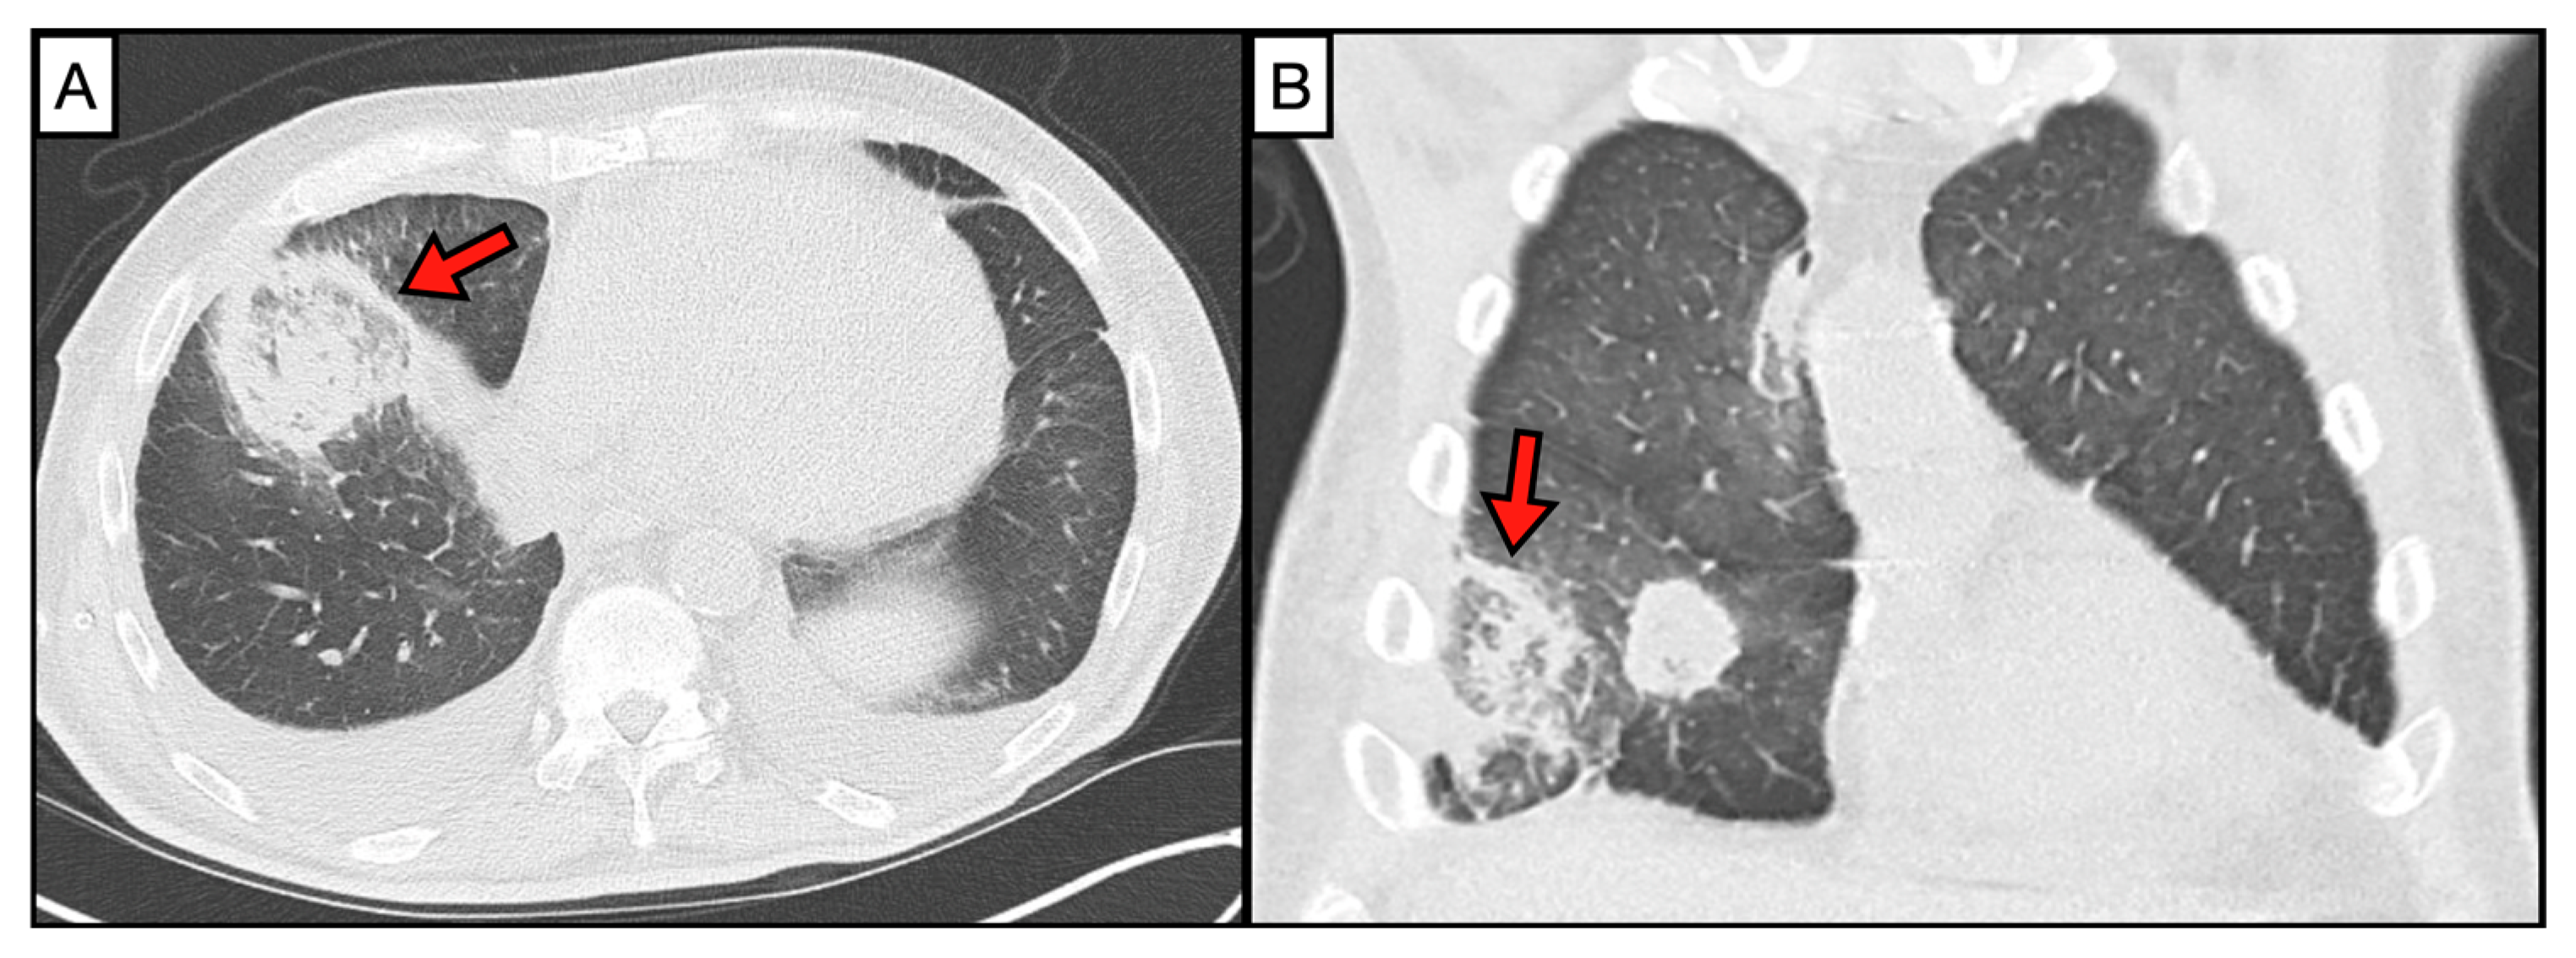

2. Imaging